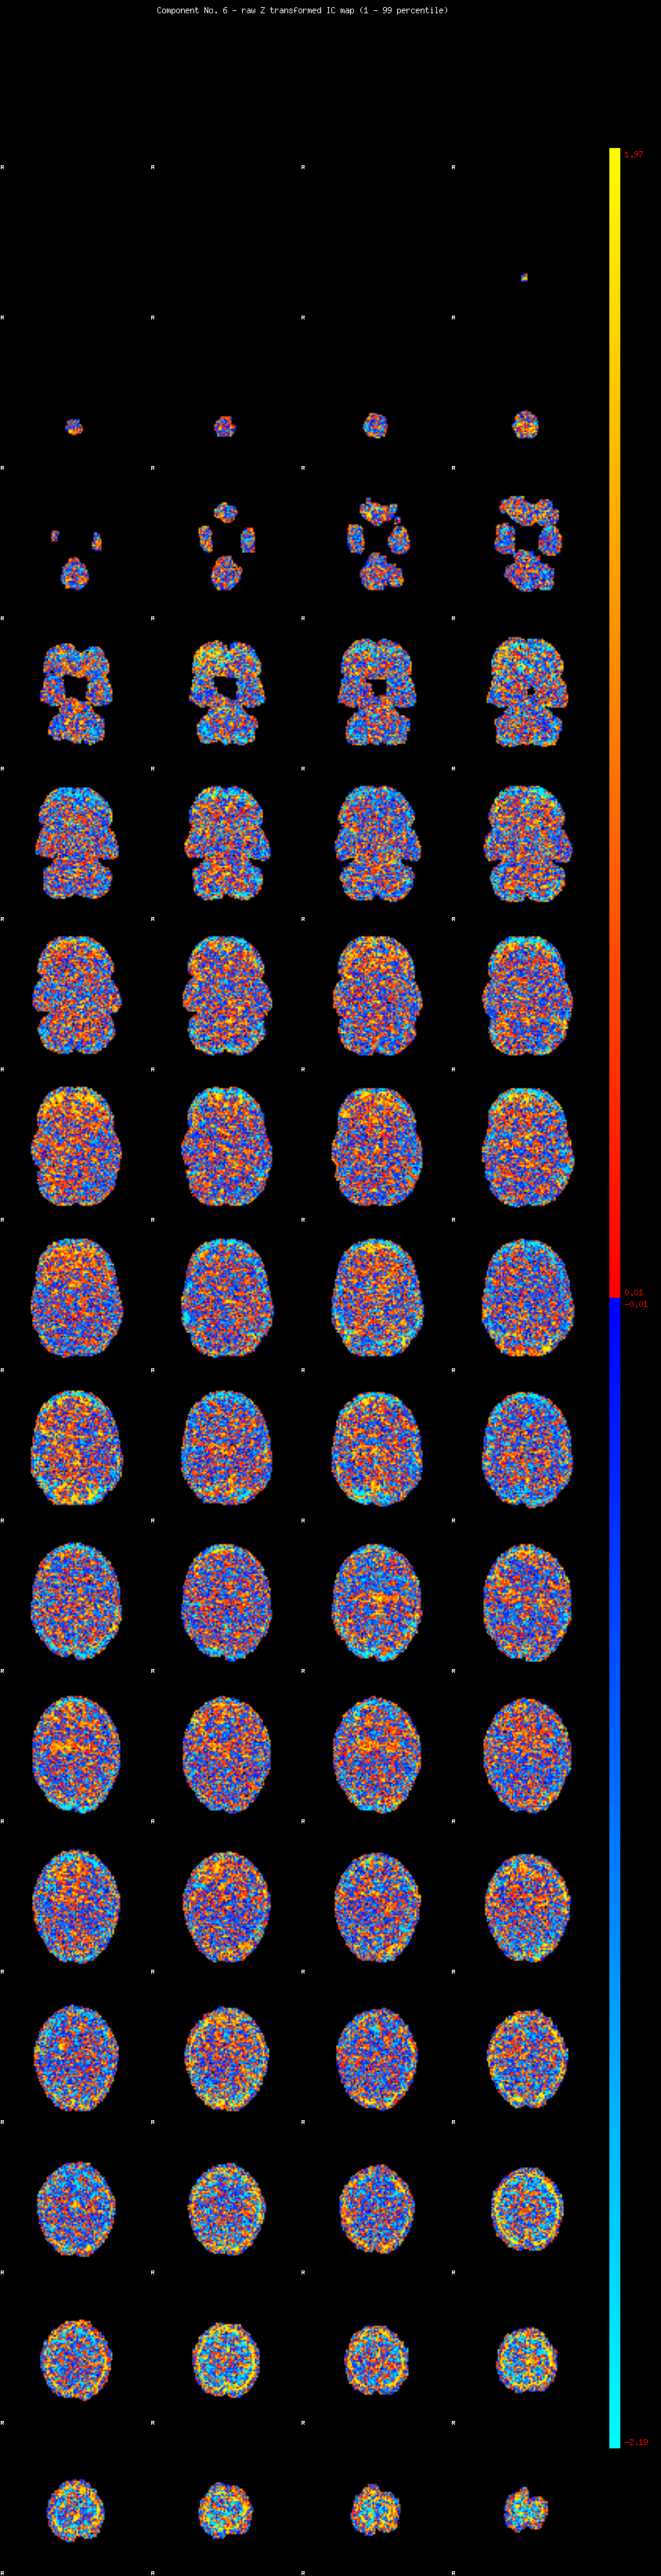

IC_6 Mixture Model fit

Means : 0.000000 2.233236 -2.341766

Vars : 1.000000 1.234664 1.479114

Prop. : 0.905979 0.035725 0.058296